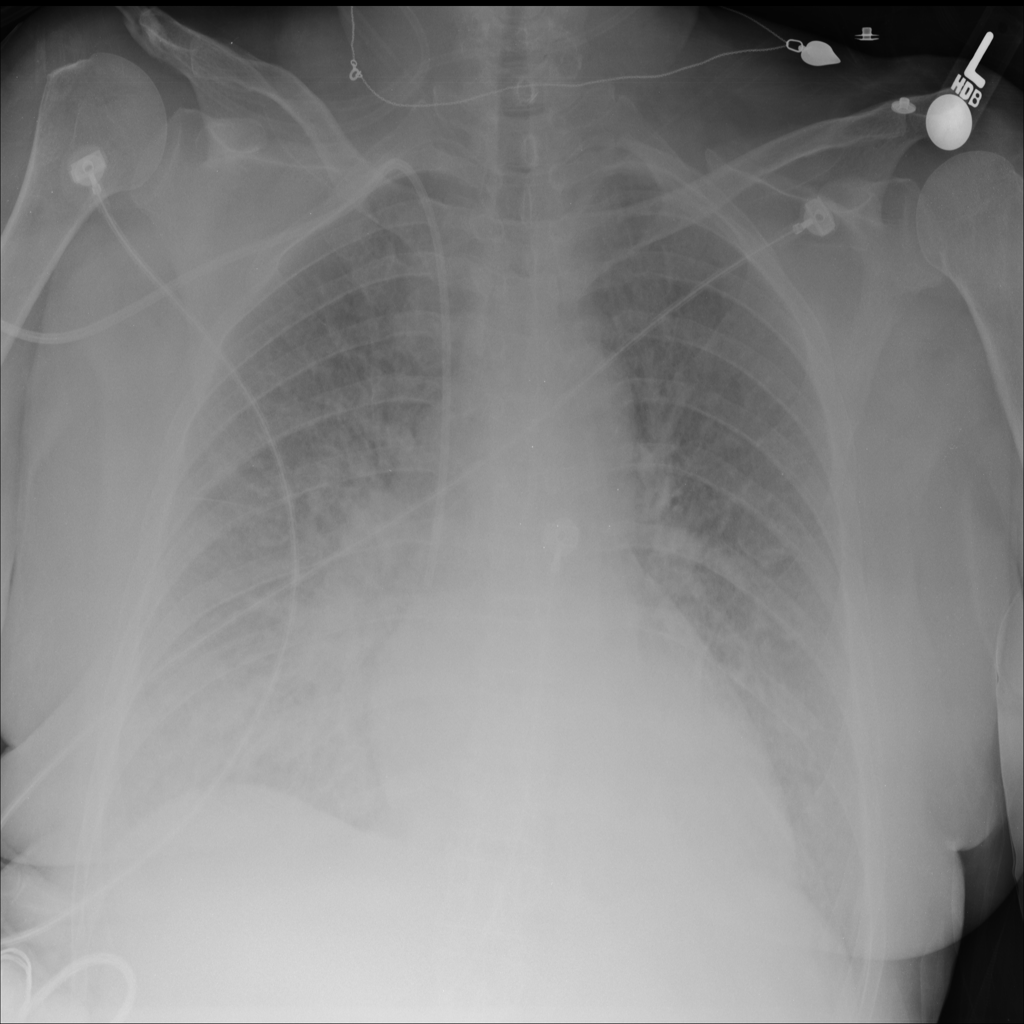

Showing up to 90 reference images for Edema.

PAT-5B86 · IMG-009Edema

PAT-5B86 · IMG-009

PA